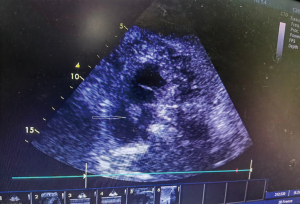

On arrival in the emergency department of our hospital, the patient had a blood pressure of 71/46 mmHg, pulse of 135 beats/min, respiratory rate of 34 breaths/min, and a warm, swollen right lower extremity. Other physical findings were unremarkable. The patient was diagnosed with massive PE with hypotension and was immediately maintained with epinephrine. TTE showed an enlarged right atrium and right ventricle, with a floating right atrial mass of 2.7 cm × 2.6 cm, prolapsing through the tricuspid valve during diastole (Figure 2). Laboratory studies showed white blood cell counts of 14,600/µL, hemoglobin of 10.9 g/dL, hematocrit of 32.1%, platelet count of 94,000/µL, cardiac troponin I level of 5.03 ng/mL, brain natriuretic peptide level of 44 pg/mL, and D-dimer level of more than 20.00 mg/L.